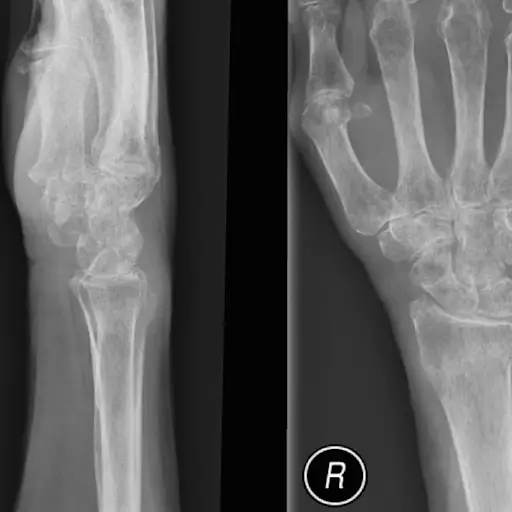

骨质疏松症手和手腕。医用x射线

Nevit Dilmen

在骨质疏松症

2017年关于风湿性关节炎风险因素的研究发现骨质疏松症患风湿性关节炎的风险增加4倍.其他研究表明,患有风湿性关节炎且有多种健康状况的人也可能患有骨质疏松症。这种联系背后可能是什么?使用类固醇以及缺乏运动,Ludmer博士说。有规律的锻炼尤其是走路或跳舞等负重运动,可以帮助防止骨质流失和关节僵硬。